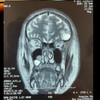

31

Dx

Sinusitis